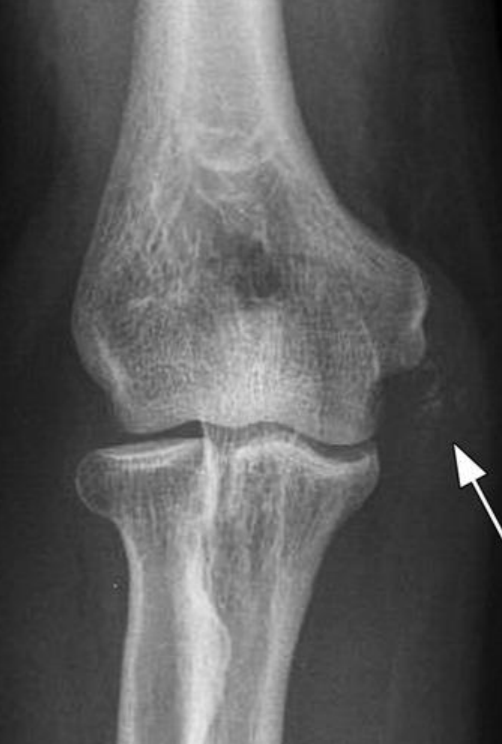

Rx en ambas patologias

Aumento de la densidad y volumen en epicondilo medial o lateral en tejidos blandos

Que significan las calcificaciones?

Lesiones crónicas

A

Epicondilitis